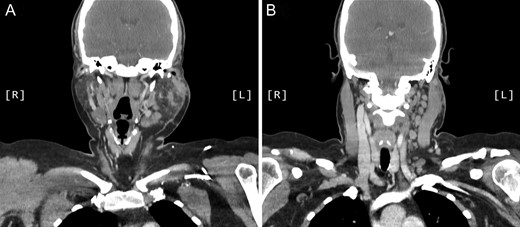

A computed tomography (CT) scan demonstrated left parotid multifocal soft tissue abnormality and enlarged left-sided cervical lymph nodes, with prominent superficial left supraclavicular fossa lymph nodes (Figs 3 and 4).

Axial CT sinuses (with contrast) showing left parotid multifocal soft tissue abnormality and enlarged left-sided cervical lymph nodes.

Coronal CT sinuses (with contrast) showing left parotid multifocal soft tissue abnormality (A) with enlarged left-sided cervical and superficial supraclavicular fossa lymph nodes (B).